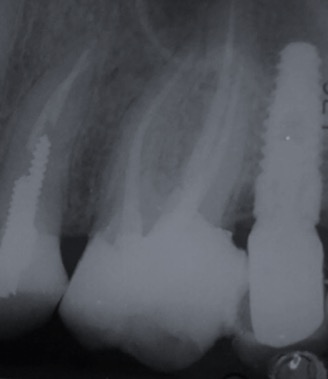

Una corretta terapia canalare con un perfetto sigillo a livello degli apici delle radici è fondamentale. I denti devitalizzati impropriamente possono creare ulteriori problemi che poi andranno a ripercuotersi sulle cure effettuate successivamente come le ricostruzioni e le corone protesiche con conseguente fallimento del piano terapeutico.

Capita spesso di incontrare denti già devitalizzati in maniera impropria che necessitano, seppur asintomatici, di essere ritrattati per evitare che i granulomi infetti visibili radiograficamente si evolvano riassorbendo tutto l’osso sottostante.